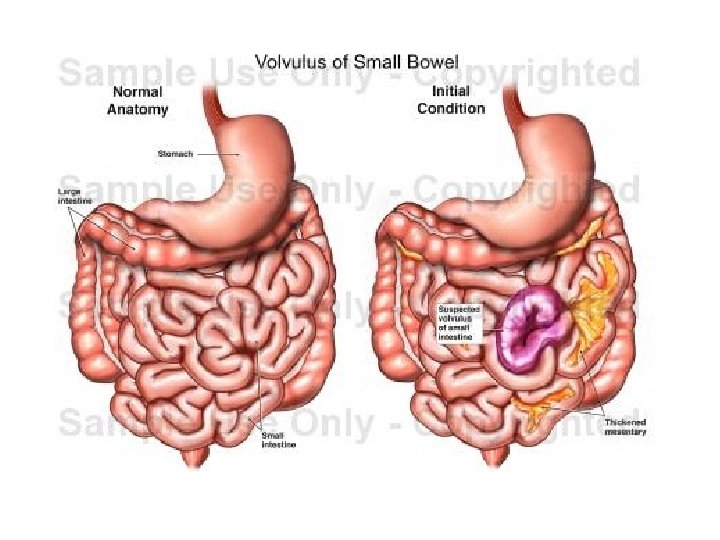

OKLUZIONET INTESTINALE

• Okluzioni Intesitnal ( Ileusi) OI eshte mos eliminimi i transitit te materialeve fekale , tretesirave digjestive e te gazrave nga pengesa te ndryshme mekanike ose parelitike.

• Okluzioni mekanik vjen nga patologji qe kane origjinen ne lumenin e zorres, ne murin e saj dhe strukturat indore fqinje. • Okluzioni intestinal nga strangulacioni shoqerohet edhe me bllokimi te menjehershem te eneve te gjakut dhe me nderprerjen e qarkullimit te gjakut.

• Okluzioni intestinal pasohet nga zgjerimi i segmentit te zorres (mbi pengese), tensionim dhe hollim te murit te saj. • Nderlikohet dhe perkeqsohet edhe qarkullimi I gjakut (venoz, kapilarve arterial) e deri ne paraliza te zorres me crregullime te permeabilitetit te murit te zorreve --crregullim te perthithjes se lengjeve dhe kriprave---duke krijuar substanca te panevojshme dhe te demshme per organizmin

Volvulus i kolonit sigmoid